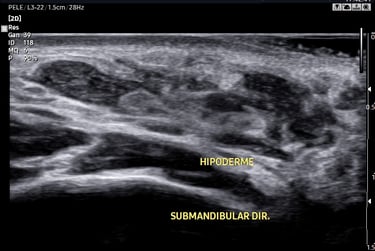

Como o Ácido Hialurônico Aparece no Ultrassom?

No exame ultrassonográfico, o depósito de ácido hialurônico pode apresentar algumas características típicas:

✔ Imagem hipoecogênica ou anecogênica – dependendo da densidade e da quantidade de fluido presente.

✔ Margens bem delimitadas – podendo ter formato arredondado ou alongado conforme a técnica de aplicação.

✔ Ausência de fluxo ao Doppler – a menos que haja reação inflamatória associada.

✔ Compressibilidade variável – podendo ser um fator diferencial entre depósitos mais recentes e os que sofreram fibrose.